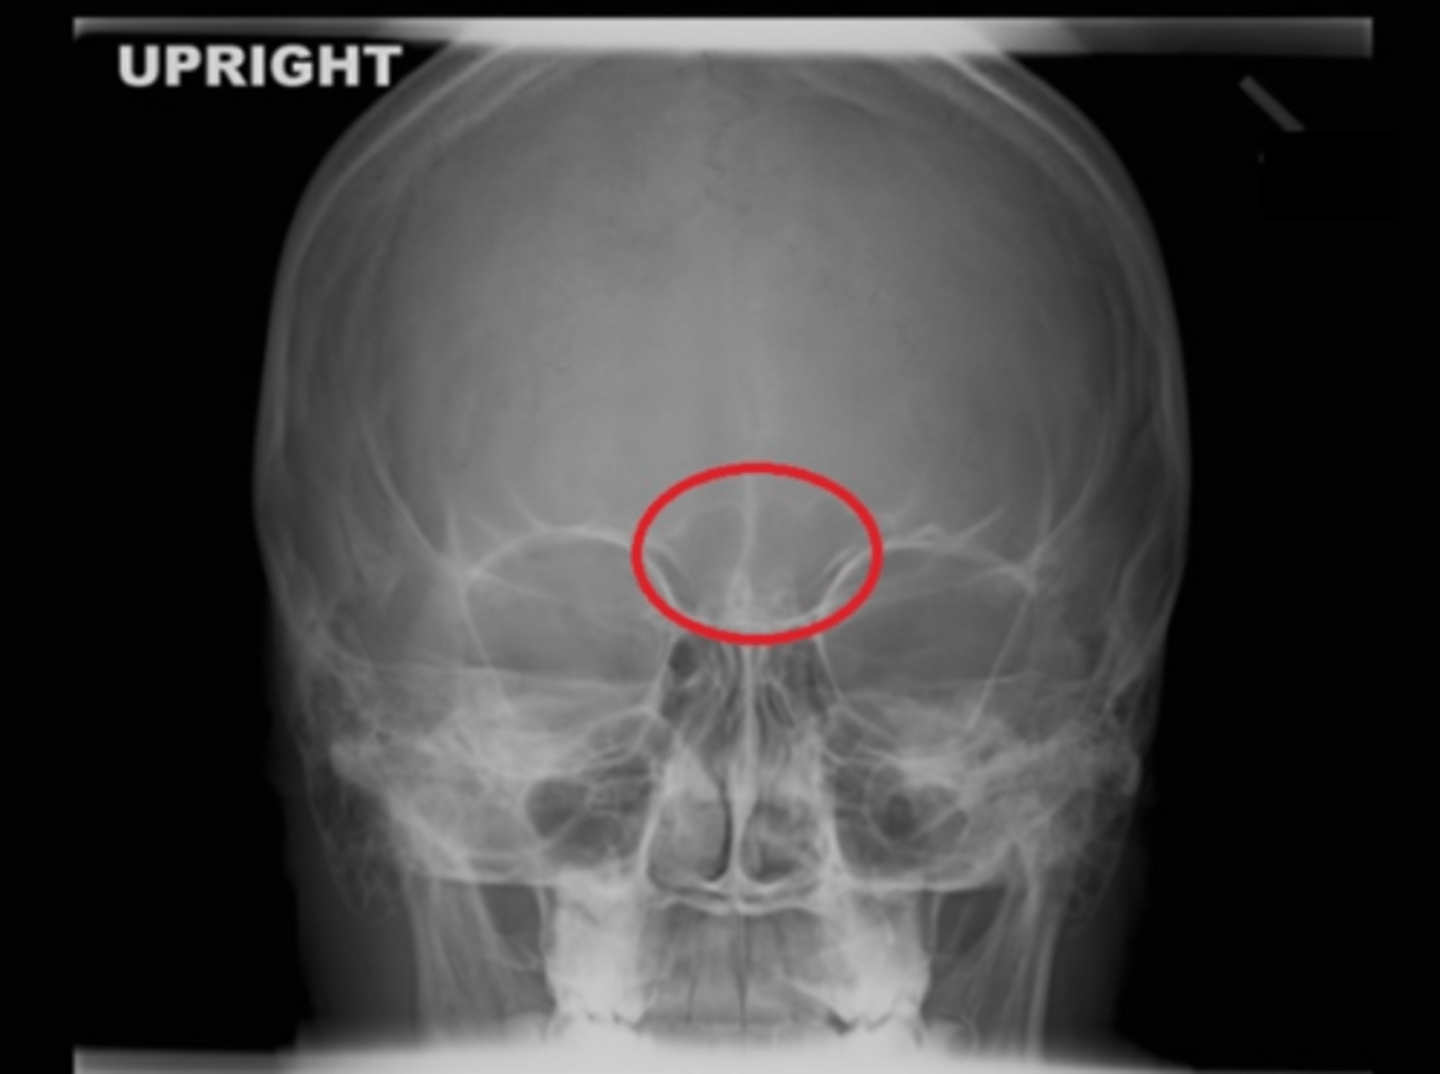

b. frontal

which sinus group is within the red circle on this image?

a. ethmoidal

c. maxillary

d. sphenoidal